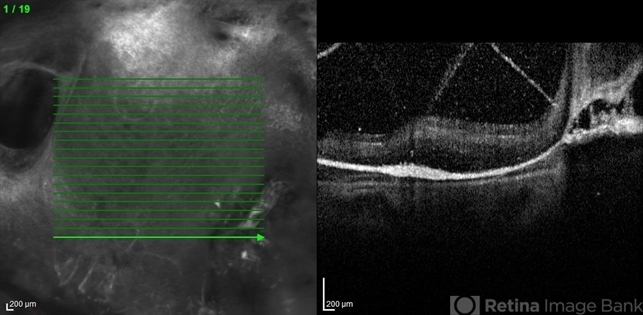

- proliferative diabetic retinopathy (PDR), optical coherence tomography (OCT)

- Soodabeh Fooladian, Negah Eye Center, Tehran, Iran

- Optical coherence tomography system

- OCT image of the right eye of a 50-year-old woman with advanced PDR.